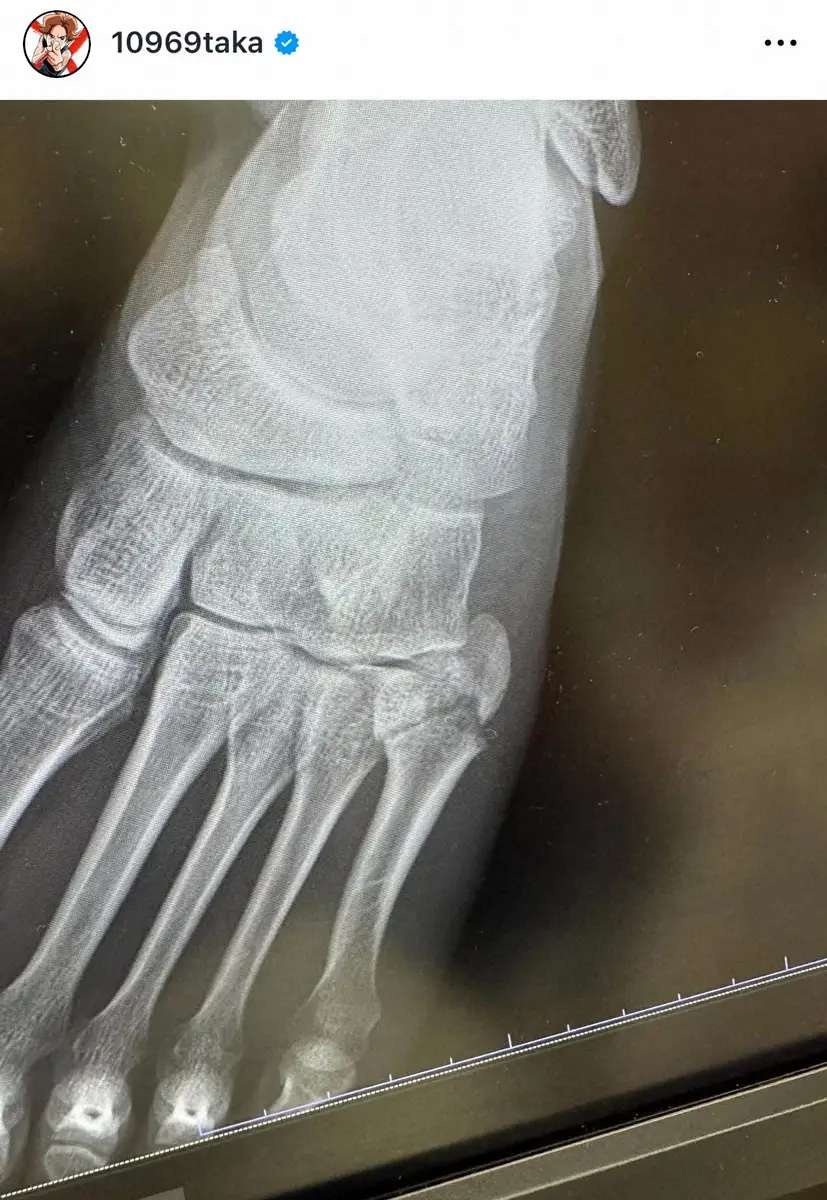

ロックバンド「ONE OK ROCK」のTaka(37)がライブ中に左足を骨折したことを1日、自身のインスタグラムで明かした。

また「でも骨折してました」と左足がギプスで固定されたショットを投稿し「あとでインスタライブしまーす」と伝えた。

その後のインスタライブで「人生初の公演中に足を骨折しました」と歌唱中に足を着いた際に「もの凄い勢いでぐちゃってなった」と左足小指の付け根を負傷したことを告白。ライブ後、すぐに病院へ行き骨折と診断された。